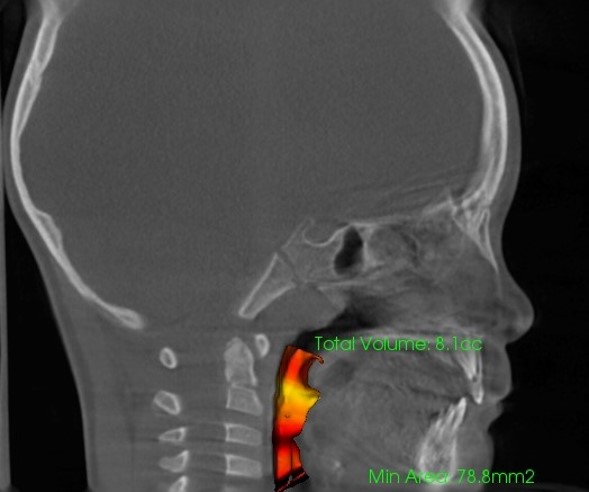

【気道容積の測定】(左:治療前8,1cc 右:治療経過21,2cc)